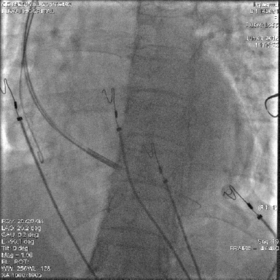

放置心房心室导线

最终影像

AP

LAO

RAO